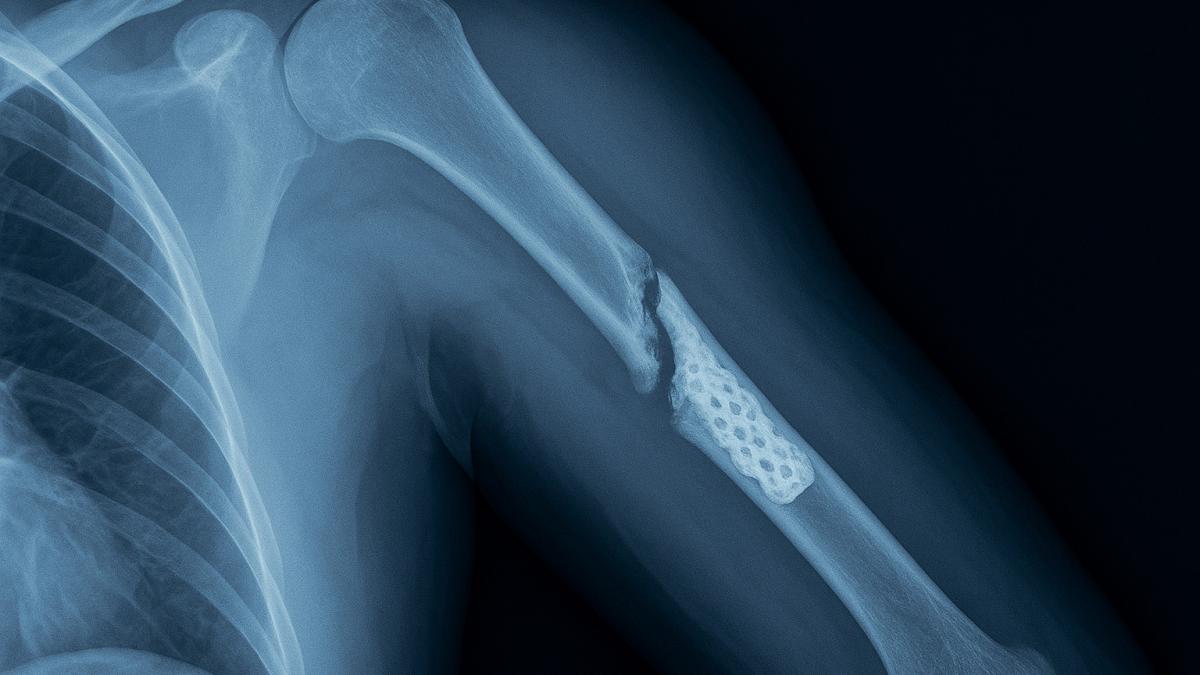

Рентген с 3D-имплантатом

Кости ломаются не от старости, а от бездействия: врачи предупредили о скрытой угрозе

Остеопороз — одно из самых коварных заболеваний костной системы, которое долгое время может протекать без симптомов. Всемирный день борьбы с ним ежегодно напоминает: здоровье костей требует внимания, особенно у людей старшего возраста.

По словам главного врача челябинской областной клинической больницы №2 Максима Угнивенко, болезнь чаще всего обнаруживается уже после перелома — и зачастую травма оказывается куда серьёзнее, чем кажется на первый взгляд.